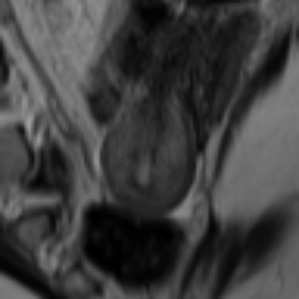

Image Reconstruction and Generation. Fig. 3 (left): Using LPIPS (AlexNet), the AE trained on FUNDUS achieved a score of on both full volumes and central slices (Z0), while the VAE reached . Applying ROI cropping to FUNDUS increased LPIPS to for the AE and for the VAE. All UMD inputs were evaluated without cropping to ROI. We evaluated 2D and 3D DDPMs using FID and LPIPS across uterine orientation classes and conditioning setups (Tab. 1): class only, class + ROI, class + text (C+T), and C+T + ROI. Example images for qualitative evaluation are shown in Fig. 2. All 2D models were trained on the central slices for evaluation, trained on all slices in the volume, FID and LPIPS increased by at minimum. Text-conditioned models without class-conditioning performed worse than class-only conditioned models in an extended ablation study. The 2D DDPM with C+T + ROI conditioning consistently achieved the best results. ROI cropping alone also improved performance, especially when combined with semantic input. In 3D, the best results came from class + ROI, though overall quality lagged behind 2D models. In Tab. 2, the ablation study shows that conditioning with class and text information combined with ROI preprocessing consistently improves image quality across DDPM and LDM models, with 2D LDMs achieving the best overall FID and LP scores.

Synthetic Datasets. The SynthUterus datasets include scans with synthetic images per class for each uterine position and are balanced to match the FUNDUS dataset distribution (Fig. 1). Two versions were generated using class and text conditioned DDPMs: full images referred to as SynthUterus and uterus-focused region of interest crops referred to as SynthUterus ROI, capturing semantic and spatial details to improve training. Ten real and ten synthetic healthy pelvic ROI MRI samples were classified by three groups: non-expert AI researchers, less experienced radiologists and experienced pelvic radiologists. Their accuracies were , and respectively, showing limited ability to distinguish real from generated images.